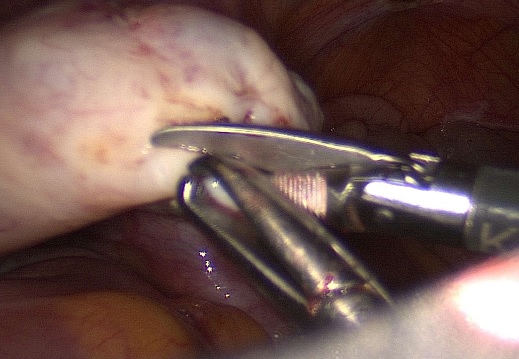

Laparoscopic view of the giant ovarian tumor.

Bipolar coagulation of the left ligamentum infundibulopelvicum.